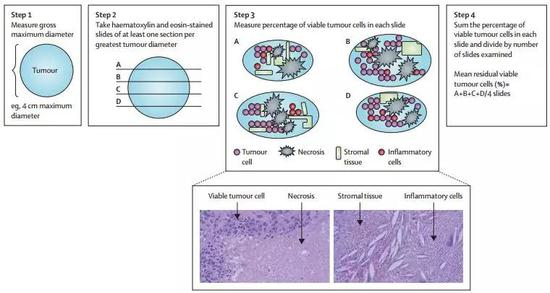

在早期肺癌免疫新辅助治疗的临床试验中,衡量试验成功与否的指标,往往不是过去常用的长期研究终点生存期(OS)和疾病无进展生存期(DFS),而是病理学显著缓解(major pathological response)。

以当今医学和生命科学发展的步伐,12年都沧海桑田了,所以业内专家普遍呼吁,把病理学显著缓解作为评价新辅助化疗效果的指标。而这个显著缓解,指的是切除的肿瘤和淋巴结中,癌细胞的占比低于10%[7]。

当然,肺腺癌和肺鳞癌的显著缓解效果也有区别,鳞癌需要相对较高的缓解程度才能实现获益,但腺癌的癌细胞比例只需要降到60%左右

如果达到了这个数字,就意味着新辅助治疗已经充分实现了术前杀灭癌细胞的目的。从过往研究来看,病理学显著缓解比客观缓解率(ORR)更能反映患者预后[8],预测DFS和OS时间,也已经有FDA认可的先例。

试验的主要终点,就是此前提到的病理学显著缓解,此外研究者们还对切除肿瘤的基因突变情况、患者体内的T细胞变化做了分析,毕竟免疫新辅助治疗还有许多未解之谜,能获得更多的数据肯定再好不过。

用研究主导者,约翰·霍普金斯医学院肿瘤免疫治疗研究所主任Drew Pardoll的话说,“我们都被惊呆了”。在手术完全切除肿瘤的20名患者中,9名患者的肿瘤已经实现显著病理学缓解,甚至有两例肿瘤中完全见不到癌细胞!

而手术前使用O药,确实调动了患者体内的T细胞进入抗肿瘤免疫状态,病理切片也证实,大量的T细胞和巨噬细胞浸润到了肿瘤当中。患者的肿瘤突变负荷(TMB),则有望作为预估疗效的生物标记物[10]。

即使是有了全新的方案,试验设计也同样需要改进,比如评价疗效的方法,就不能像过去一样靠影像学的缓解标准进行,最好把T细胞亚群测定、肿瘤突变负荷这些新检查,能做的都做了才好。